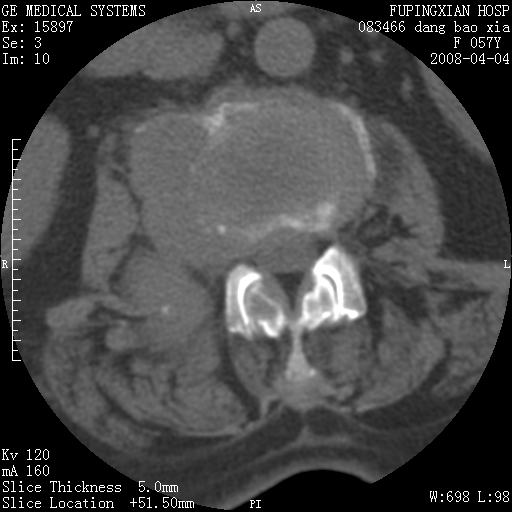

标题: CT12677:女性,57岁,疼痛数月。 [打印本页]

标题: CT12677:女性,57岁,疼痛数月。

椎体及附件骨质破坏同时伴软组织肿块,首先考虑恶性肿瘤。

椎体及附件骨质破坏,伴软组织肿块,首先考虑恶性骨肿瘤,建议提供正侧位片。

病灶见多部位;转移瘤

查原发灶吧,考虑转移瘤。老年人出现骨肿瘤首先要除外转移瘤及骨髓瘤。

椎体及附件溶骨性破坏,周围巨大软组织肿块,首先考虑转移瘤。